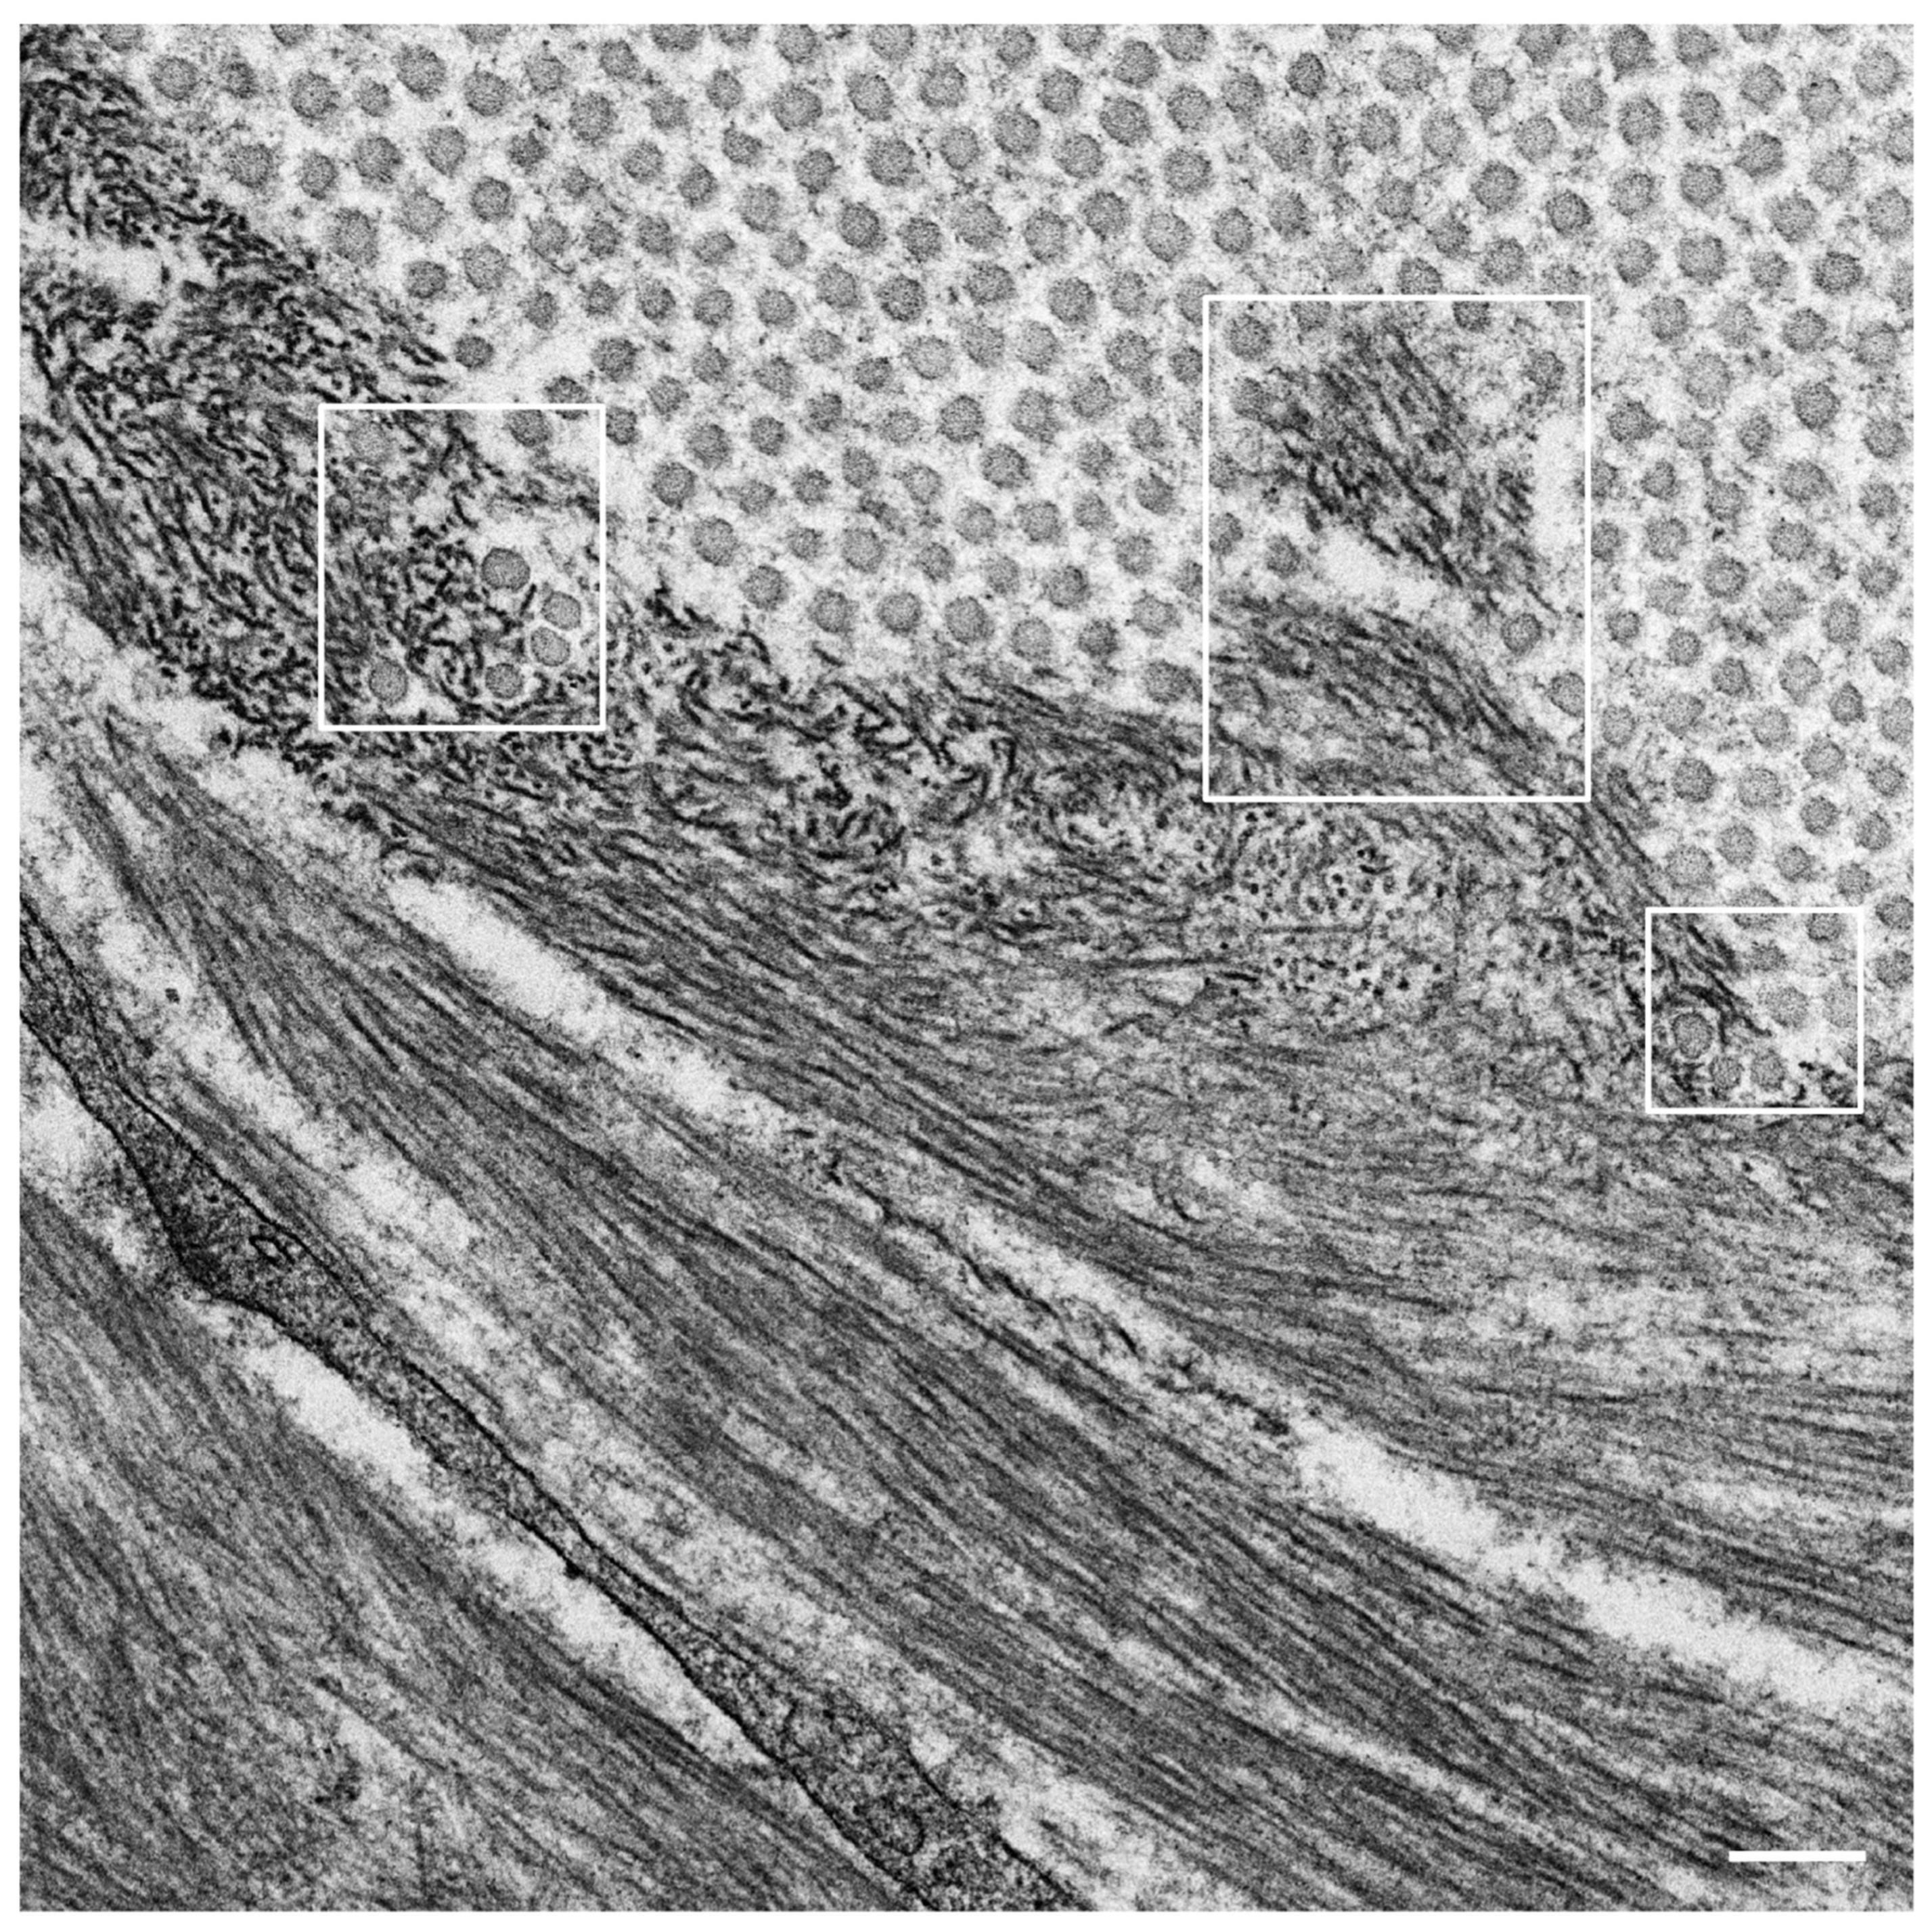

- Koike, H.; Katsuno, M. The Ultrastructure of Tissue Damage by Amyloid Fibrils. Molecules 2021, 26, 4611. [Google Scholar] [CrossRef] [PubMed]

- Koike, H.; Ikeda, S.; Takahashi, M.; Kawagashira, Y.; Iijima, M.; Misumi, Y.; Ando, Y.; Ikeda, S.-I.; Katsuno, M.; Sobue, G. Schwann cell and endothelial cell damage in transthyretin familial amyloid polyneuropathy. Neurology 2016, 87, 2220–2229. [Google Scholar] [CrossRef]

- Koike, H.; Nishi, R.; Ikeda, S.; Kawagashira, Y.; Iijima, M.; Sakurai, T.; Shimohata, T.; Katsuno, M.; Sobue, G. The morphology of amyloid fibrils and their impact on tissue damage in hereditary transthyretin amyloidosis: An ultrastructural study. J. Neurol. Sci. 2018, 394, 99–106. [Google Scholar] [CrossRef] [PubMed]